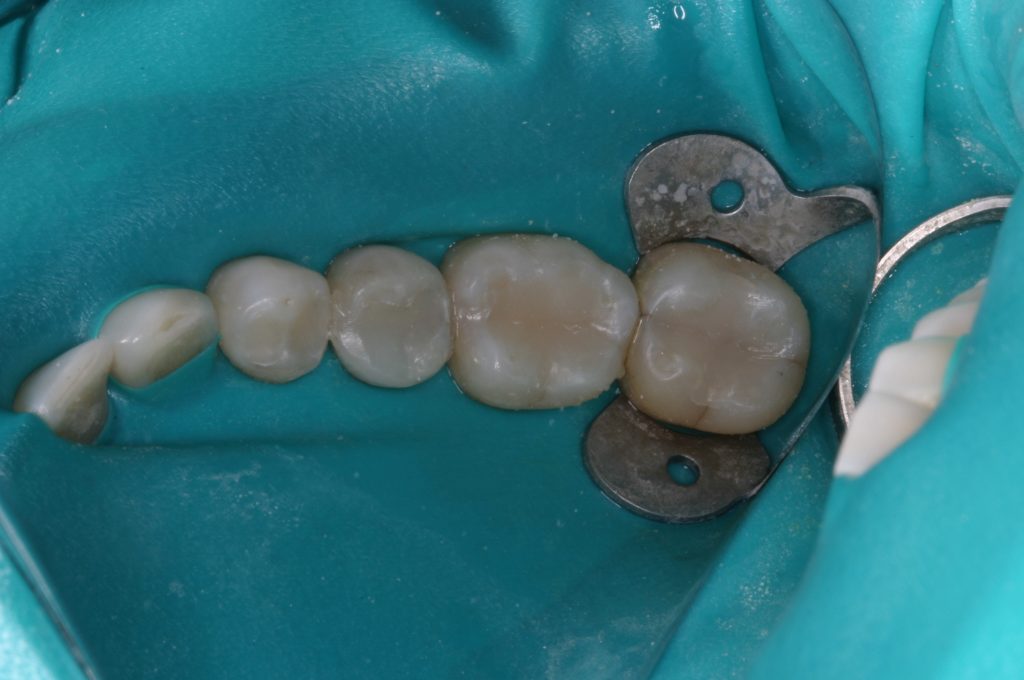

We are committed to creating a healthy environment for all of our patients. We are happy to discuss any or all of these topics with you and are committed to giving you all the information you need to make an informed healthcare choice. Dr Whicker is a member of the Holistic Dental Association and the International Association of Mercury Toxicology. We have all the equipment, materials, and protocols needed to safely remove mercury fillings.

- Mercury-Free Environment: Abstains from using mercury fillings, safeguarding you from potential toxic exposures and advocating for environmental conservation.